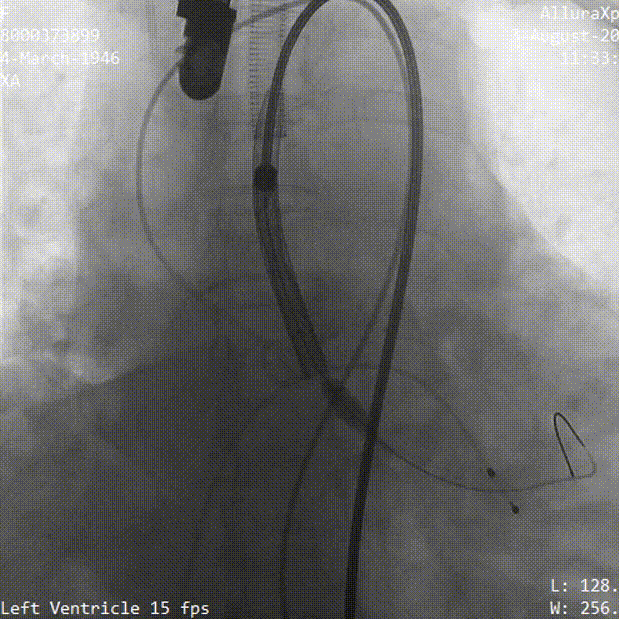

术中影像

工作位造影 瓣膜位置良好

冠脉灌注良好

最终位造影 形态良好 位置理想

无瓣周漏 即刻跨瓣压差为3mmHg